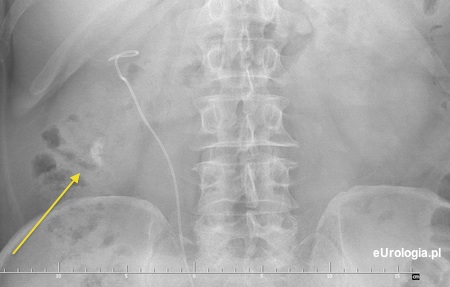

Kamica resztkowa dolnego kielicha po ESWL złogu w miedniczce nerkowej

Kruszenie dużego kamienia w nerce ESWL może być nieskuteczne i często wymaga leczenia uzupełniającego - ponowne ESWL lub PCNL. Czasami konieczne jest endoskopowe usunięcie fragmentów złogu z moczowodu - URS. W Pańskim przypadku część fragmentów rozkruszonego złogu wpadła do dolnego kielicha nerki dając obraz kamicy resztkowej. Nie jesteśmy w stanie odpowiedzieć czy złóg z miedniczki został w całości usunięty - rozkruszony. Poniżej może Pan zobaczyć przykładowe zdjęcia pacjenta z kamicą resztkową po ESWL.